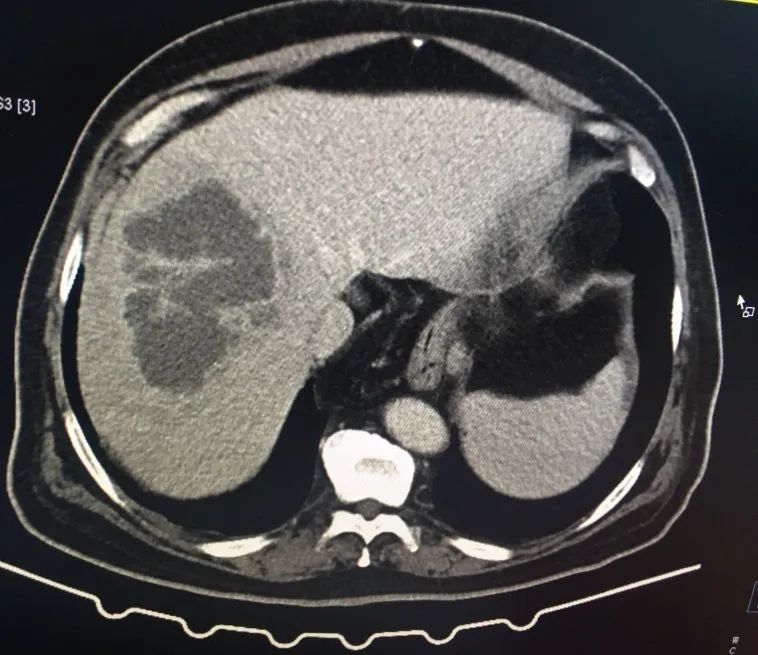

腹部CT: 肝右叶低密度灶,胆囊结石,建议增强CT;

腹部增强CT: 肝右叶多发肝脓肿、胆囊结石、腹主动脉硬化、食管裂孔疝、左肾囊肿。